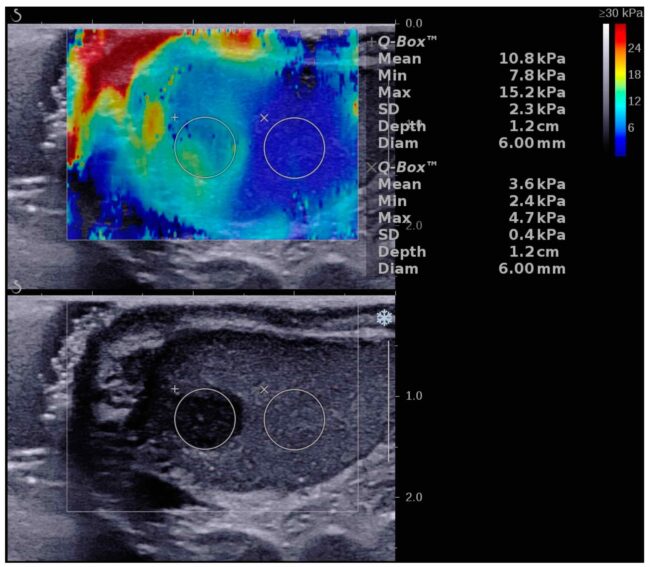

Еластографія в урології — це сучасний неінвазивний метод ультразвукової діагностикищо, що оцінює жорсткість тканин передміхурової залози нирок, статевого члена, яєчок та сечового міхура для виявлення фіброзу та інших патологій. Переваги методу: Еластографія яєчок — це метод ультразвукової діагностики, який оцінює жорсткість тканин калитки. Переваги та підготовка Еластографія статевого члена — це спеціалізоване ультразвукове дослідження, яке вимірює жорсткість тканин органа.…